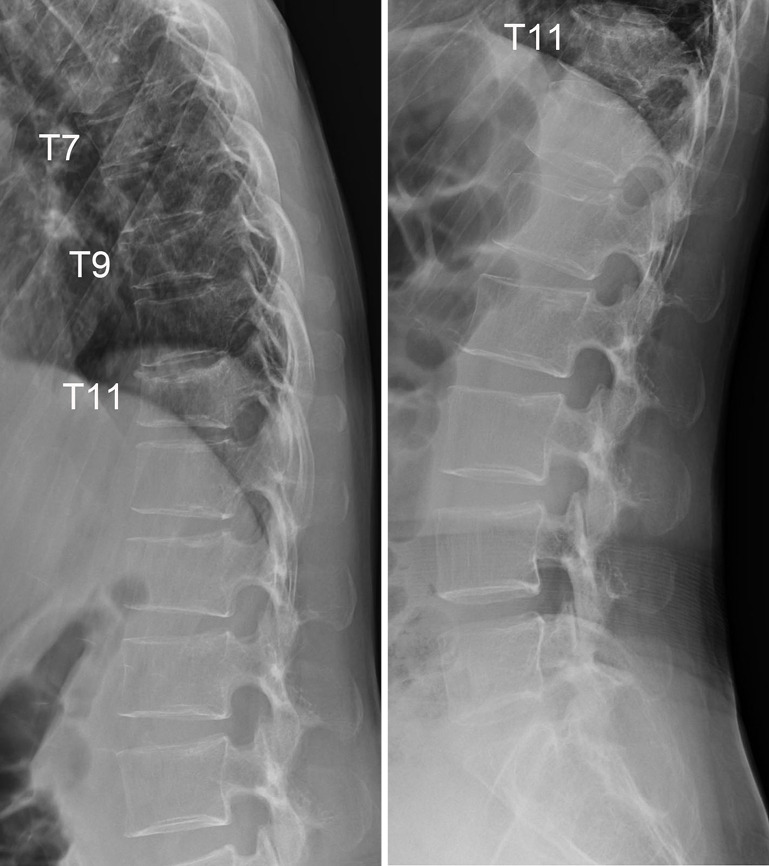

背景:妊娠和哺乳期相关骨质疏松症(PLO)是一种罕见的影响妊娠晚期和哺乳期早期妇女骨骼脆弱的疾病。PLO患者经历多发、快速发作的椎体骨折并发展为后凸,当诊断和治疗延迟时,预后较差。由于没有针对PLO患者的标准治疗方案,治疗应单独计划。近年来,romosozumab已被公认为治疗严重骨质疏松症患者最有效的药物之一。因为它可以在短时间内显著增加绝经后骨质疏松症妇女的骨密度(BMD),它对治疗骨质疏松症进展迅速且骨折风险高的患者是有用的。在这里,我们报告一例PLO合并多椎体骨折用romosozumab治疗。据我们所知,这是首个单独使用romosozumab治疗PLO的报道。病例描述:一名中年产后和哺乳期妇女在怀孕9个月时背部疼痛,分娩后恶化。PLO的诊断基于多发胸椎和骶骨脆性骨折和低骨密度。她接受罗莫索单抗治疗,背部疼痛逐渐消退。经过12个月的罗莫索单抗治疗,她的腰椎骨密度比基线增加了22.1%,并且没有发生进一步的骨折。结论:12个月的romosozumab治疗成功改善了重症PLO患者的临床状况,BMD显著增加。

Case description: A middle-aged postpartum and lactating woman experienced back pain at 9 months of pregnancy, which worsened after delivery. PLO was diagnosed based on multiple thoracic vertebral and sacral fragility fractures and low BMD. She was treated with romosozumab, and her back pain gradually subsided. After 12 months of romosozumab treatment, her lumbar spine BMD increased by 22.1% from baseline, and no further fractures occurred.